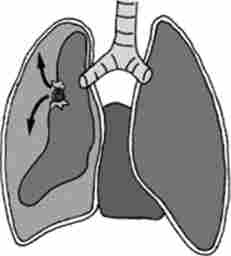

Мал. 25.2. пневмоторакс (схема ^

Пневмоторакс. Пневмоторакс - скупчення повітря в плевральній порожнині, що веде до спадання тканини легені, зміщення середостіння в здорову сторону, здавлення кровоносних судин середостіння, опущення купола діафрагми, що в кінцевому підсумку викликає розлад функції дихання і кровообігу (рис. 25.2).